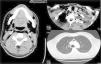

A 30-year-old patient came to the emergency department due to crepitations in the face, neck and thorax after the extraction of the right mandibular third molar the previous day. The patient referred no dyspnea, pain or tumefaction. Upon exploration, the patient was hemodynamically stable, with an oxygen saturation of 100% and evident subcutaneous emphysema on the right side of the face, laterocervical region and right side of the upper thorax. Work-up was normal; cervical and thoracic radiography showed important subcutaneous emphysema and pneumomediastinum, and computed tomography (CT) was done (Fig. 1). The patient was admitted to hospital for prophylactic antibiotics and observation. The evolution was favorable, with a progressive reduction in the emphysema, with no apparent complications, and the patient was therefore discharged four days later.

Cross-sectional CT images of the mandibular, inferior cervical and superior mediastinal areas. There is observed widespread emphysema that dissects the bilateral cervical muscle planes and affects the parapharyngeal and prevertebral spaces, floor of the mouth, submandibular space and posterior cervical space, reaching the mediastinum and causing pneumomediastinum. These findings are asymmetrical and more evident on the right side.